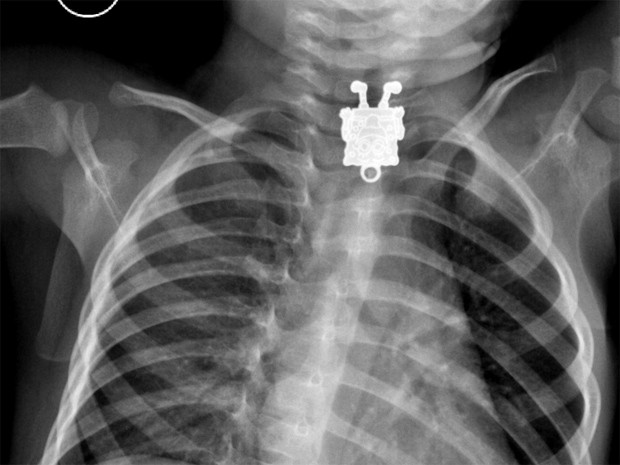

Raio-X mostrou pingente de Bob Esponja no esôfago de garoto de 1 ano (Foto: Cortesia/Ghofran Ageely/Radiopaedia.org)Raio-X mostrou pingente de Bob Esponja no esôfago de garoto de 1 ano (Foto: Cortesia/Ghofran Ageely/Radiopaedia.org)

Médicos da Arábia Saudita se surpreenderam ao examinar um raio-X de um garoto de 1 ano e 4 meses que aparentemente tinha se engasgado com um objeto. Um Bob Esponja pôde ser visto com riqueza de detalhes no esôfago do paciente. O objeto foi retirado pelos médicos sem complicações e o garoto passa bem.

Detalhes mostra Bob Esponja na radiografia (Foto: Cortesia/Ghofran Ageely/Radiopaedia.org)

Detalhe mostra Bob Esponja na radiografia (Foto:

Cortesia/Ghofran Ageely/Radiopaedia.org)

A médica conta que o primeiro raio-X, tirado do corpo de lado, mostrou um pequeno objeto que os médicos pensaram ser um grampo ou outro acessório de cabelo.

A radiografia frontal, porém, mostrava claramente do que se tratava: “‘Bob Esponja’, eu gritei! Fiquei impressionada com os detalhes visíveis. Você podia ver as sardas, sapatos e dedos. Incrível”, escreveu Ghofran em um e-mail ao “LiveScience”. Ela conta que os médicos tiraram o pingente do esôfago do garoto e o liberaram para ir para casa no mesmo dia.